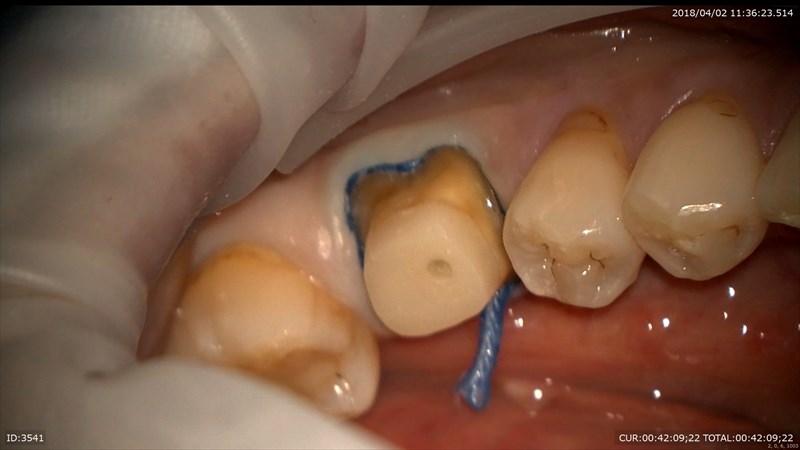

そしてそこから少し形成

2本目

OK

この部分が歯根の立ち上がりです